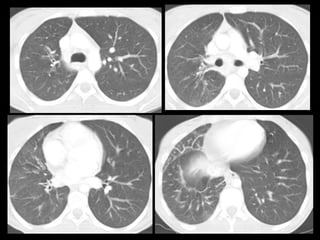

• Otro caso

Varón de 56 años que consulta por hemoptisis

• Otro caso Varónde 56 años que consulta por hemoptisis